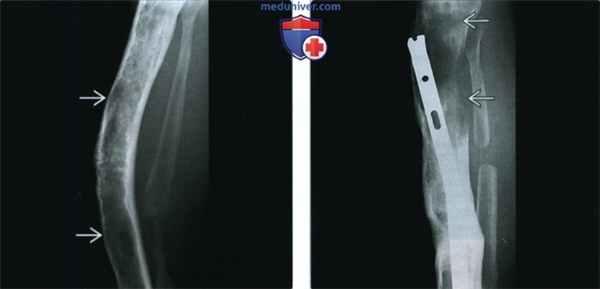

(Слева) Рентгенография в боковой проекции: классические признаки фиброзной дисплазии (ФД). Трабекулы замещены матовым матриксом, отмечается вспученность кости и фестончатость кортикального слоя. Выражено переднее искривление кости, которое было устранено посредством корригирующей остеотомии с интрамедуллярной фиксацией стержнем.

(Справа) Рентгенография в боковой проекции, этот же пациент через несколько лет: визуализируются признаки консолидации в зоне остеотомии. Однако в проксимальном отделе большеберцовой кости визуализируется новый деструктивный литический очаг, который оказался зоной редкою перерождения ФД в фибросаркому.